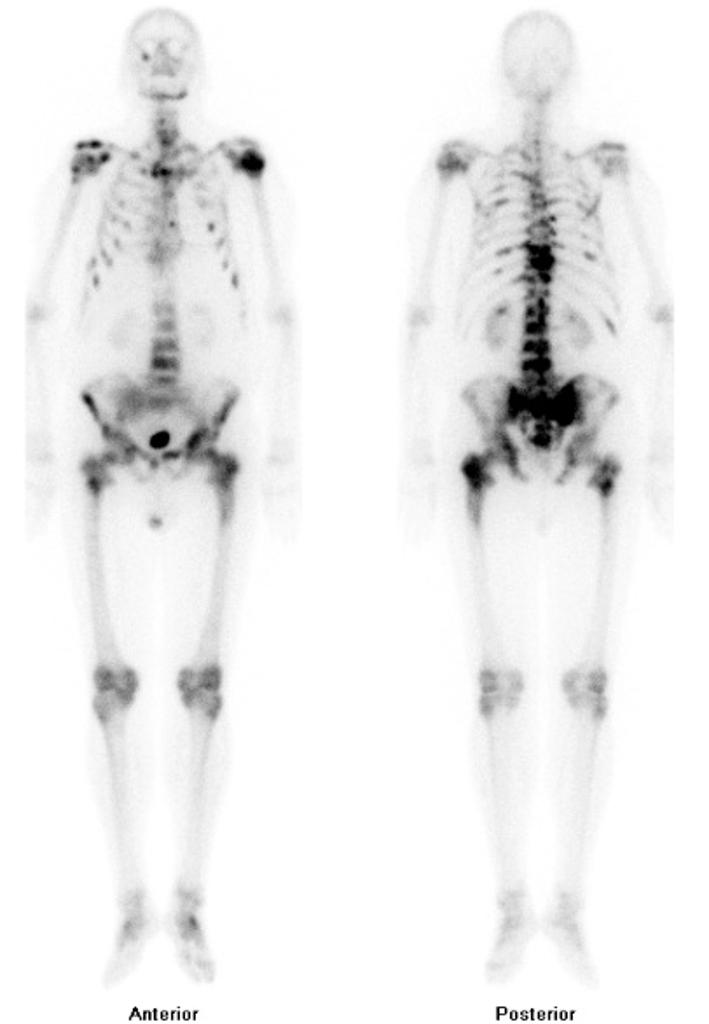

& BONE SCAN In Cancer

जब आपके स्तन में जो गांठ है उसमें CANCER है यह जांच में पाया जाता है तब पेट की सोनोग्राफी और बोन स्कैन किया जाता है.

यह दोनों ही जांच आपके पूरे शरीर में कैंसर कितना फैला हुआ है यह देखने के लिए किए जाते हैं.

पेट के सोनोग्राफी में कैंसर की गांठ आपके लीवर में, या अन्य कहीं जगह पर है कि नहीं यह देखा जाता है.

बोन स्कैन जांच में आपके शरीर की पूरी हड्डियों में कोई कैंसर के अंश दिख रहे हैं या नहीं यह देखा जाता है.

बोन स्कैन एक स्पेशल जांच है. यह कुछ लिमिटेड लैब में ही होती है. इसका खर्चा भी 6 से 8000 होता है. इसमें आपको नसों में एक इंजेक्शन दिया जाता है और एक स्पेशल मशीन द्वारा आपके पूरे शरीर का GAMMA किरणों से एक्सरे किया जाता है.

इसकी रिपोर्ट आपको दूसरे दिन मिल सकती है और आपका कैंसर कितना फैला है इसकी जानकारी इस रिपोर्ट से मिलती है.

इन दोनों जांच से आपके कैंसर को कौन सा ट्रीटमेंट देना चाहिए यह तय होता है.